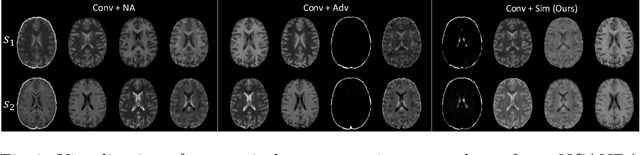

Abstract:Multi-modal MR images are widely used in neuroimaging applications to provide complementary information about the brain structures. Recent works have suggested that multi-modal deep learning analysis can benefit from explicitly disentangling anatomical (shape) and modality (appearance) representations from the images. In this work, we challenge existing strategies by showing that they do not naturally lead to representation disentanglement both in theory and in practice. To address this issue, we propose a margin loss that regularizes the similarity relationships of the representations across subjects and modalities. To enable a robust training, we further introduce a modified conditional convolution to design a single model for encoding images of all modalities. Lastly, we propose a fusion function to combine the disentangled anatomical representations as a set of modality-invariant features for downstream tasks. We evaluate the proposed method on three multi-modal neuroimaging datasets. Experiments show that our proposed method can achieve superior disentangled representations compared to existing disentanglement strategies. Results also indicate that the fused anatomical representation has great potential in the downstream task of zero-dose PET reconstruction and brain tumor segmentation.